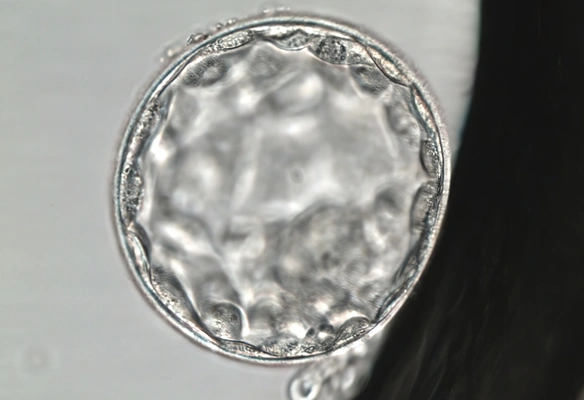

Assisted hatching

Assisted hatching is a specialised laboratory technique that involves breaking or thinning the zona pellucida, the protective layer surrounding the embryo. This technique is particularly used in the following cases:- Before carrying out PGT (Preimplantation Genetic Testing)

- When the embryologist observes that the zona pellucida is too thick or rigid

- In patients with a history of implantation failure

It is a laboratory technique in which the zona pellucida (the outer layer of the embryo) is thinned or carefully opened using a laser. This makes it easier for the embryo to break free and attach to the endometrium.